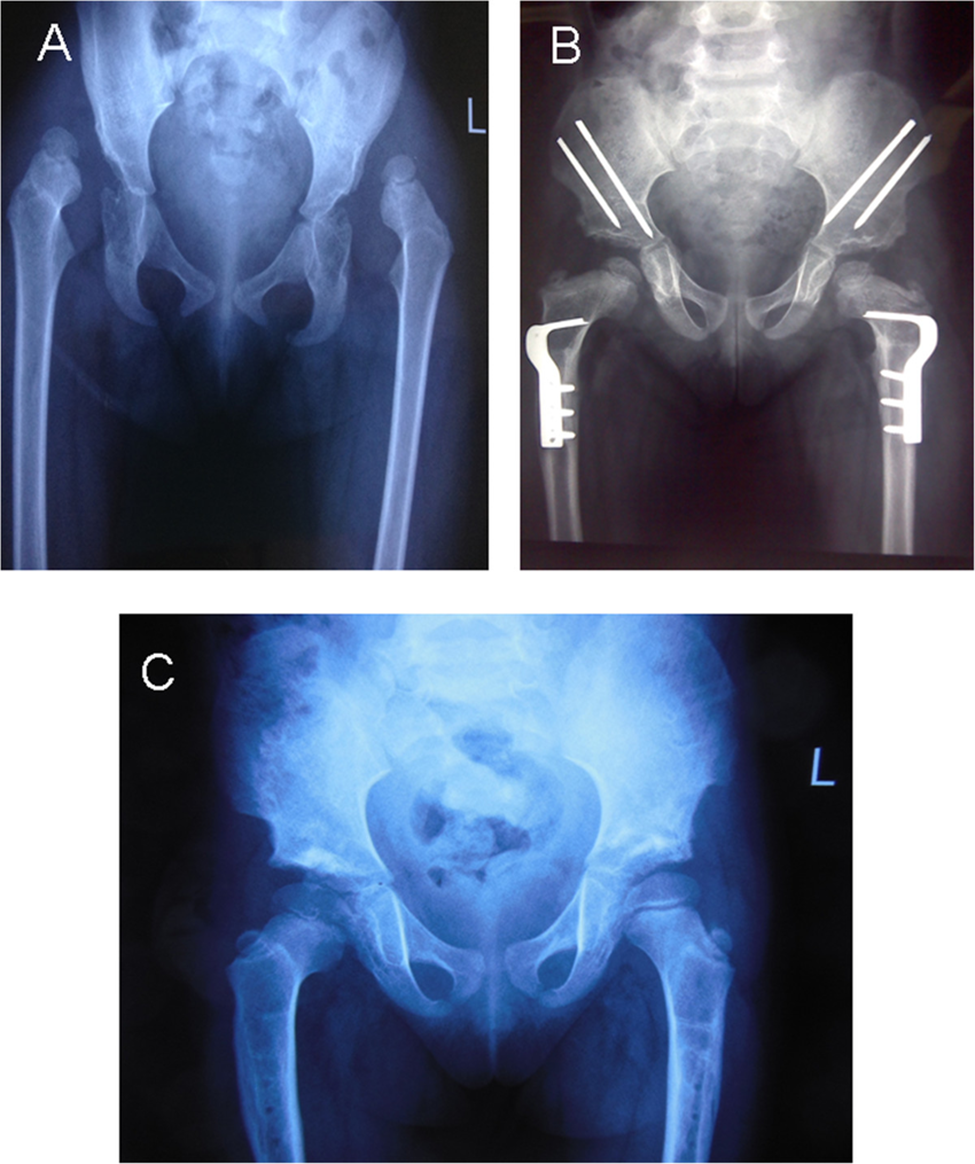

Figure 1